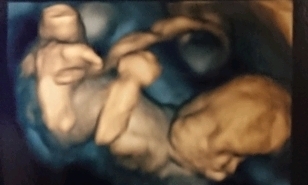

18週1日(18w1d・性別不明)|ぴーさよ さん(30歳)

エコー写真撮影時のエピソード:

初めての4Dエコーでした。 いつも見てるエコーとは違い立体的に見えて愛しさが増しました(^^) 他の人がこれを見たらただのホラー写真ですが。

少し恥ずかしいのか横を向いて隠れようとしていました!正面ではないけどお口をパクパクと動かしてくれて元気一杯で先生にも順調ですねと言われとても安心したのと、ほんとにお腹にいるんだなぁーって改めて思いました(^^)